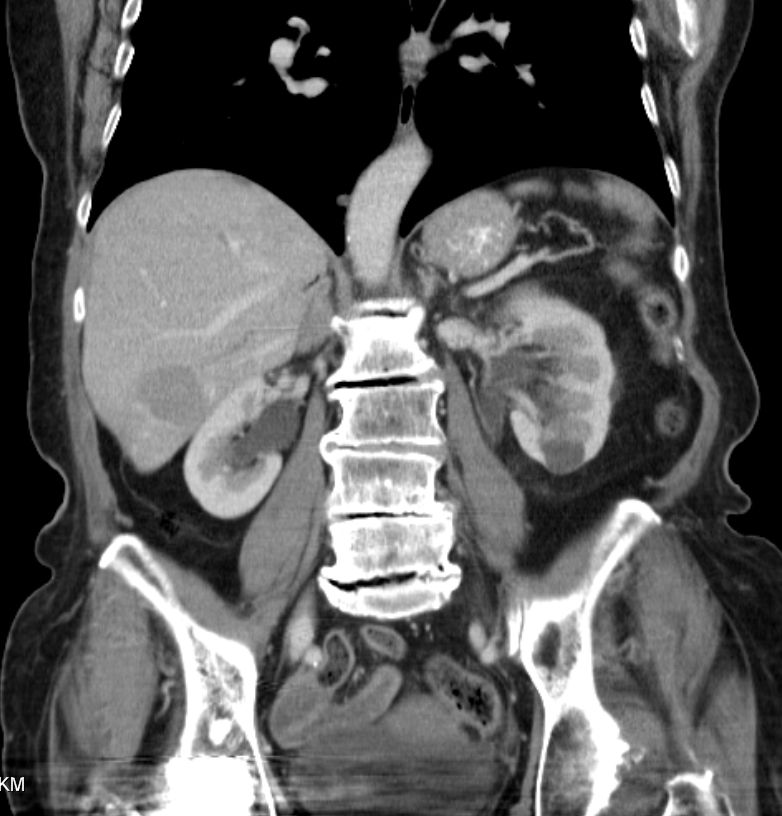

79-jährige Frau, die vor einem Jahr eine Klatskin-Tumor pT2 pNo Mo LoV1 G2 entwickelte. Operation Ro. Jetzt Lebermetastase. Chemotherapie mit Gemcitabine: Progress.![]() |